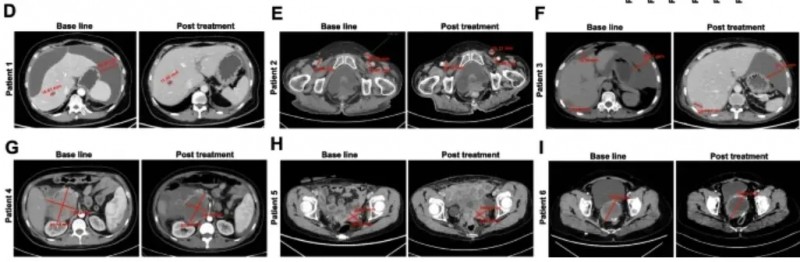

更值得关注的是,该疗法部分缓解率达33.3%:2例患者实现“部分缓解”(肿瘤缩小≥30%),其中患者1肝转移灶缩小31%且腹腔积液消失,患者2可测量病灶总最大直径缩小42%。

该研究共纳入10例转移性结直肠癌(CRC)患者,中位年龄58岁(范围48.8-67岁),其中80%(8/10)伴肝转移、50%(5/10)伴肺转移,所有患者入组后均接受CEA CAR-T细胞静脉输注。

结果显示:10例既往治疗进展(PD)的患者中,7例经CAR-T治疗后达病情稳定(SD),肿瘤直径仅轻微变化,其中P3、P5患者稳定期超30周(7.5个月)。